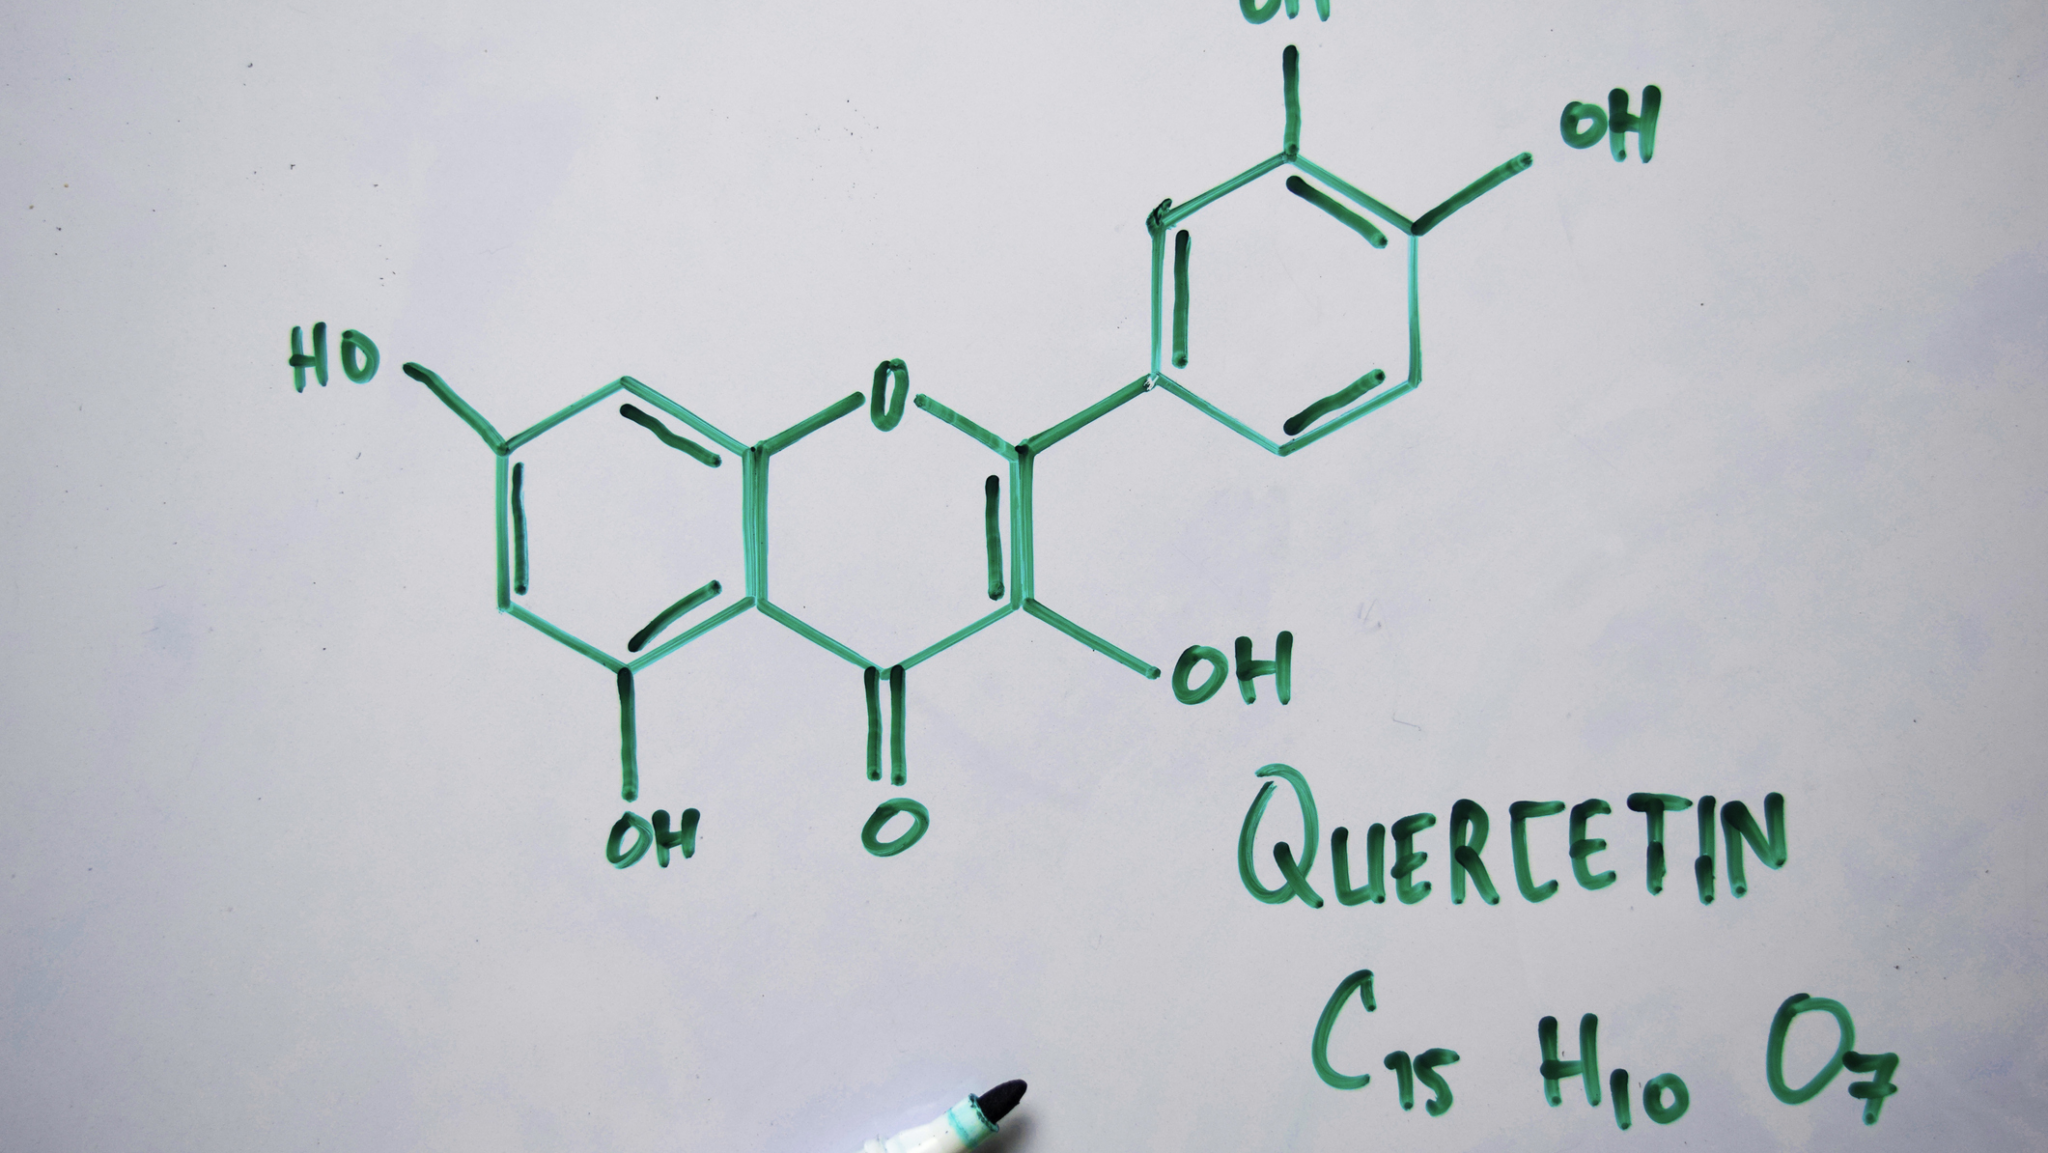

A new U.S. study published Friday in JAMA Health Forum warns that eliminating fluoride from community water systems could lead to increased tooth decay in children and drive up dental costs by an estimated $9.8 billion over five years. “Fluoride replaces weaker ions within tooth enamel, making it stronger and less susceptible to tooth decay … Read more